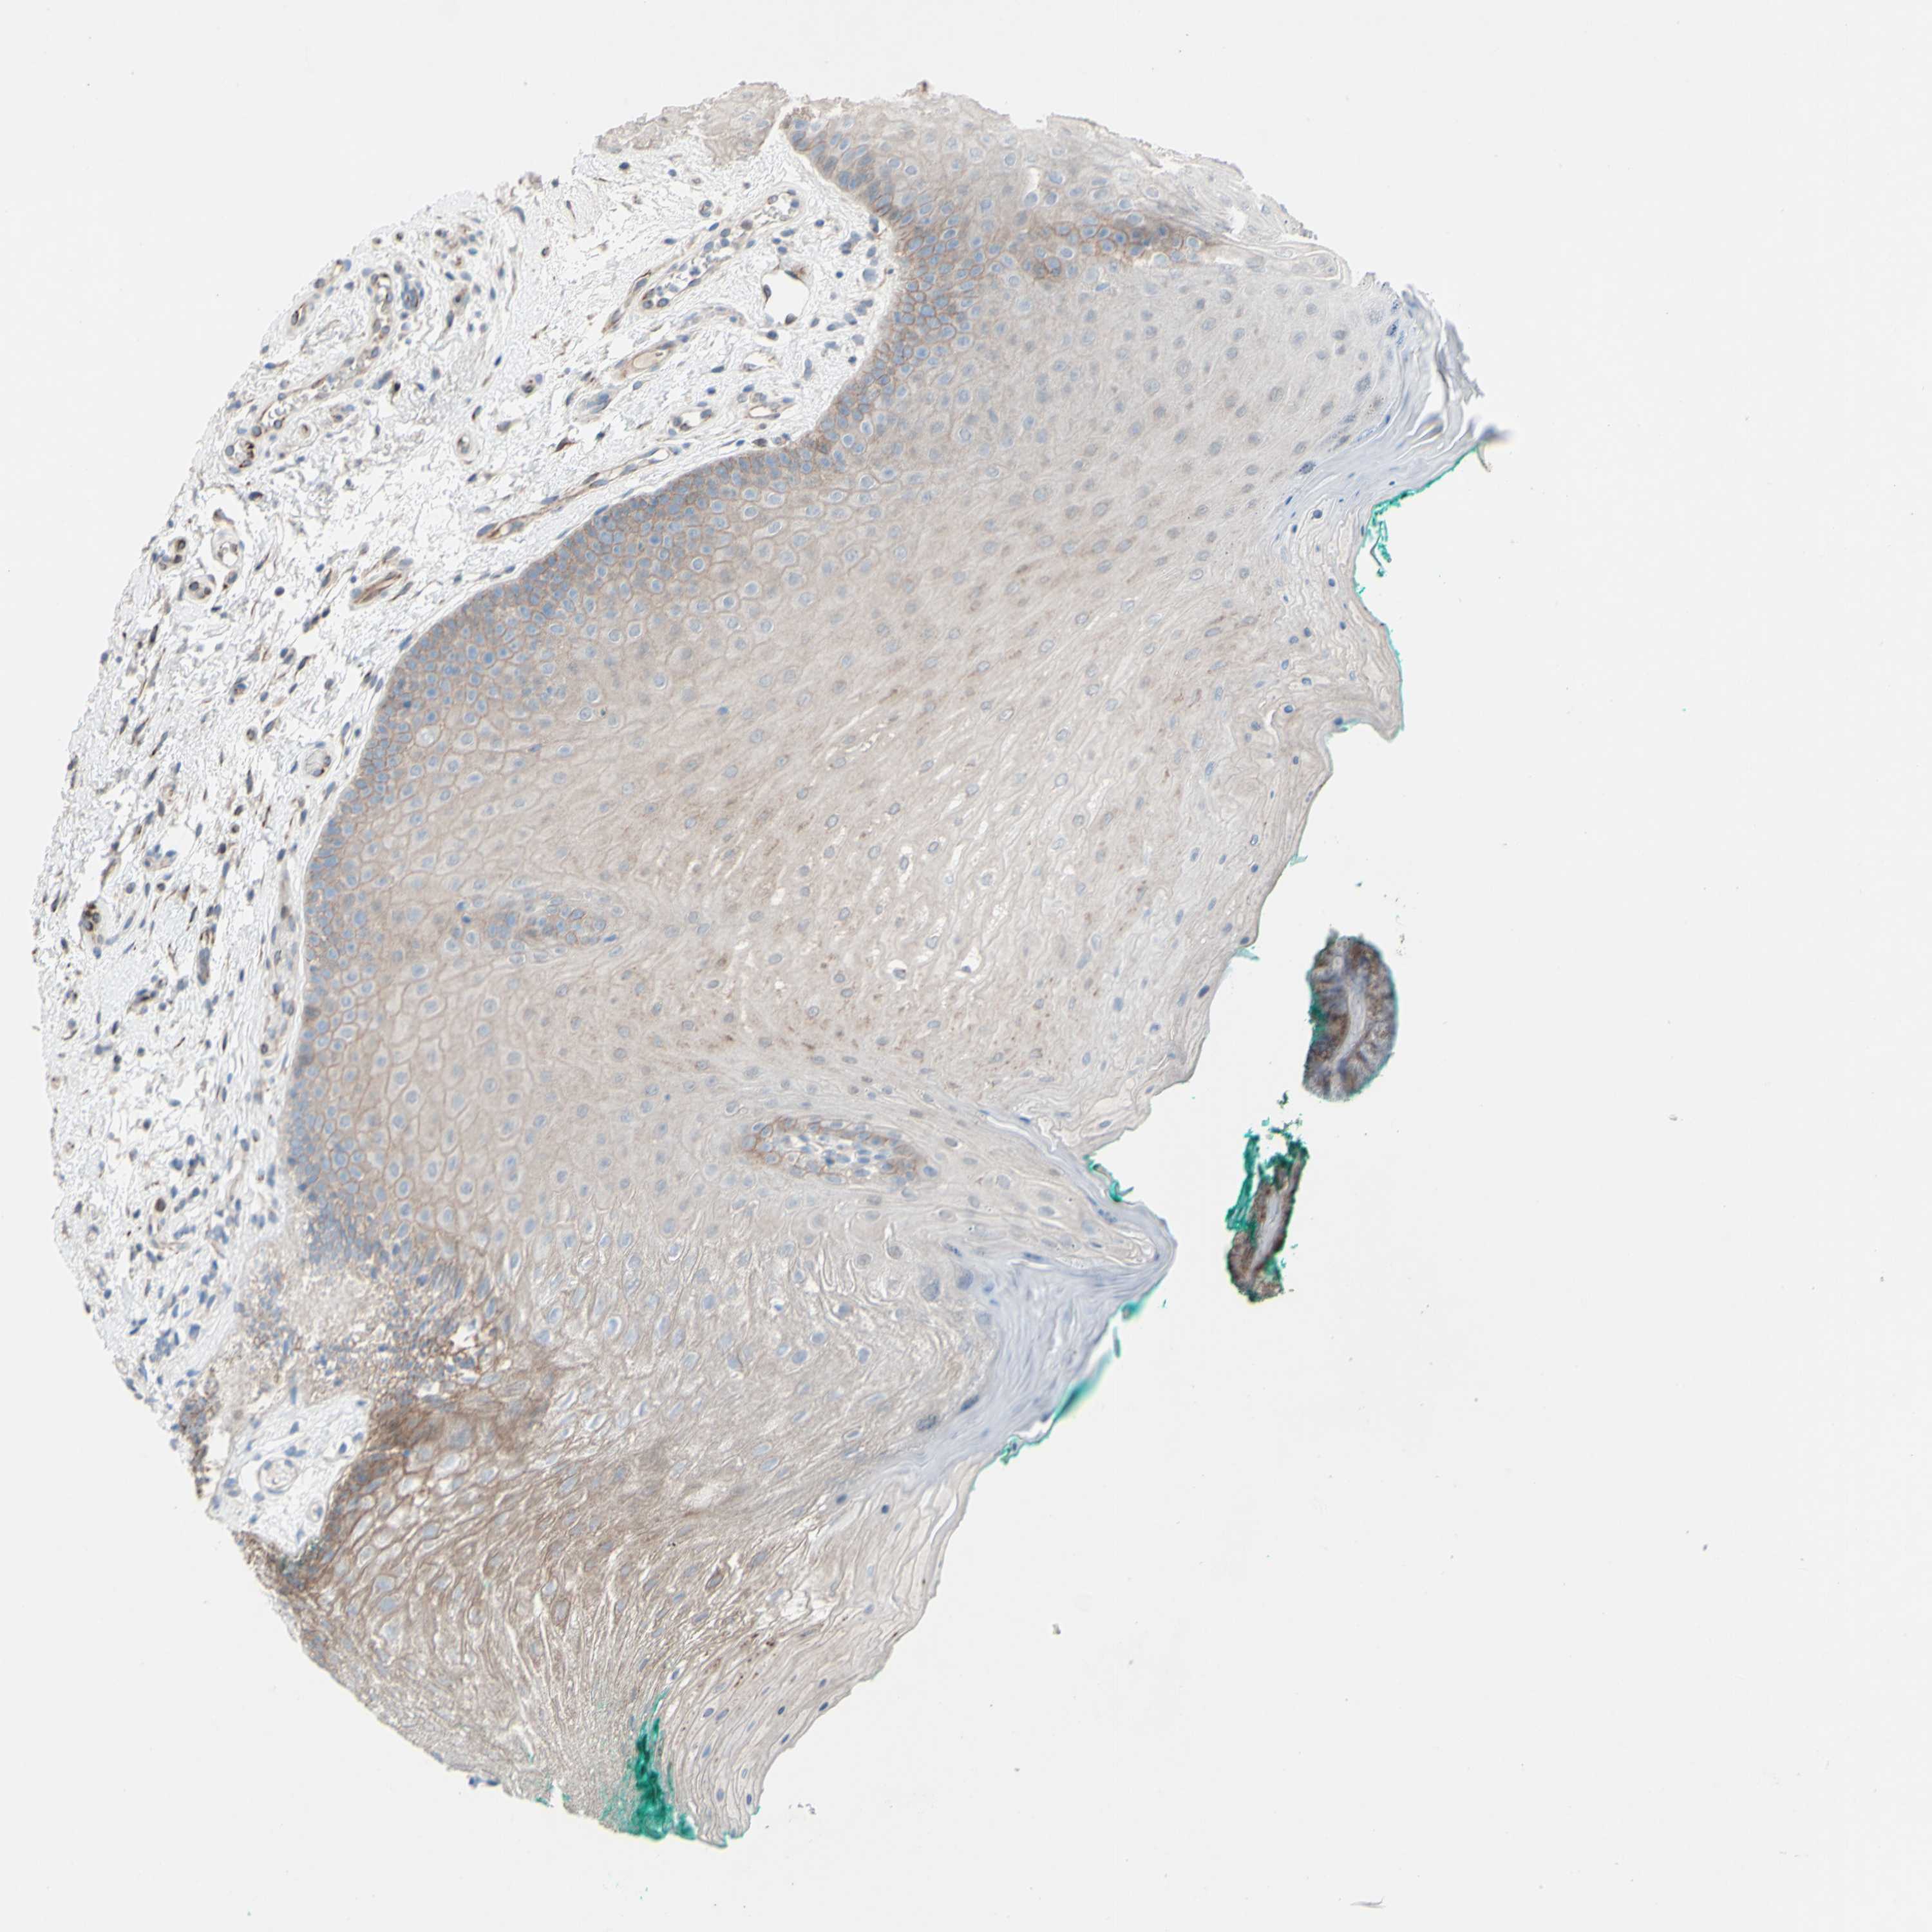

CDCP1